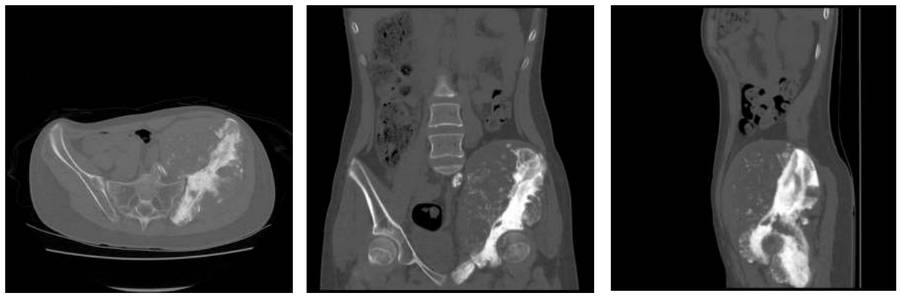

Before the surgery: The CT scan shows a large tumor tissue that has caused bone destruction affecting the entire lumbar 5th vertebra, sacrum, and iliac wing, and extending into the soft tissue.